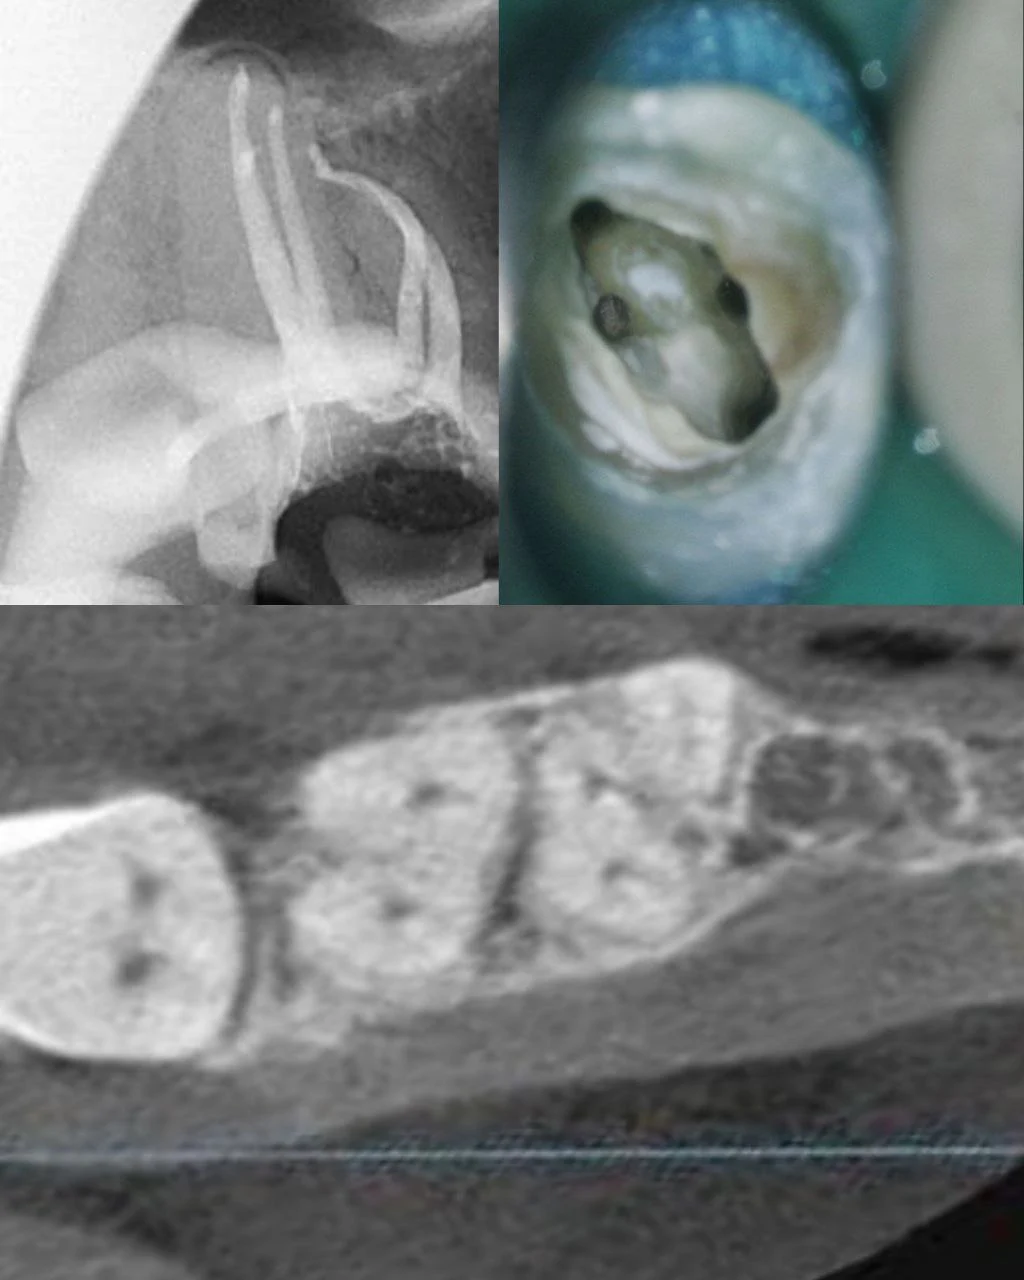

Что вы видите на аксиальном срезе на уровне устьев

При открытии аксиального среза на уровне устьев (обычно 2–4 мм апикальнее цементо-эмалевой границы) вы видите:

✅ Контур коронки зуба — внешняя граница

✅ Дентин — серая масса вокруг

✅ Пульпарная камера — тёмная полость в центре

✅ Каналы — тёмные точки, овалы (просветы каналов)

✅ Перешейки между каналами — тонкие дентинные мостики

Ключевое отличие от прицельного снимка

На прицельном рентгене каналы наслаиваются друг на друга (проекция).

На аксиальном срезе вы видите их РЕАЛЬНОЕ расположение в пространстве — без наложений.